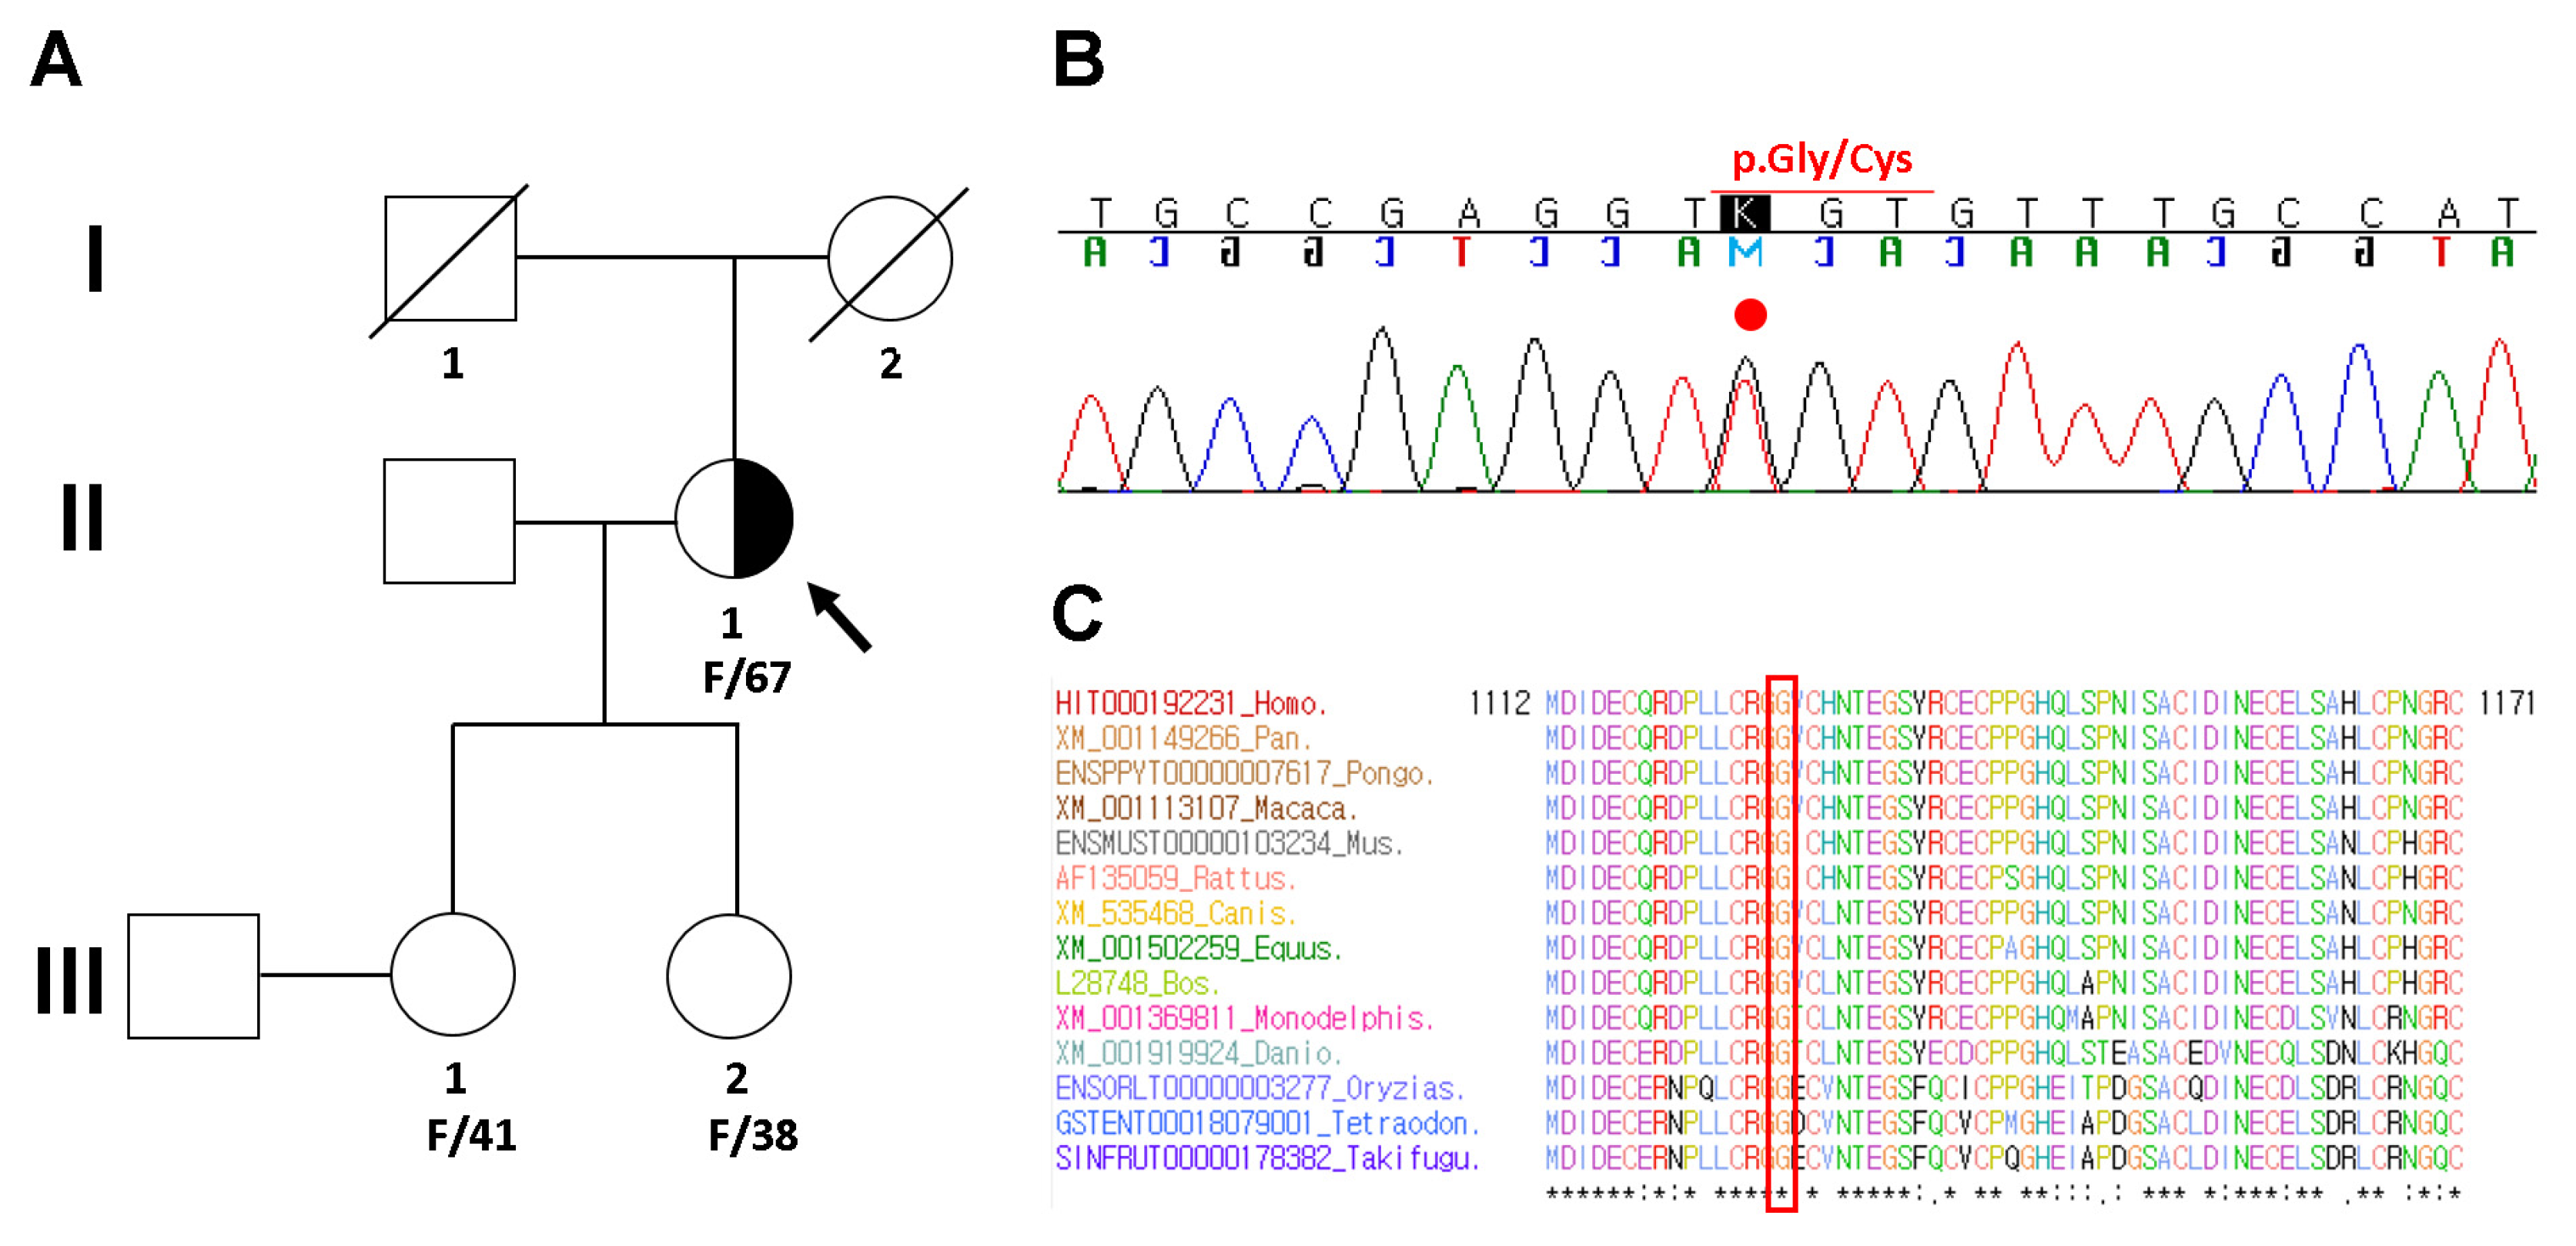

2. Case Presentation

3. Discussion